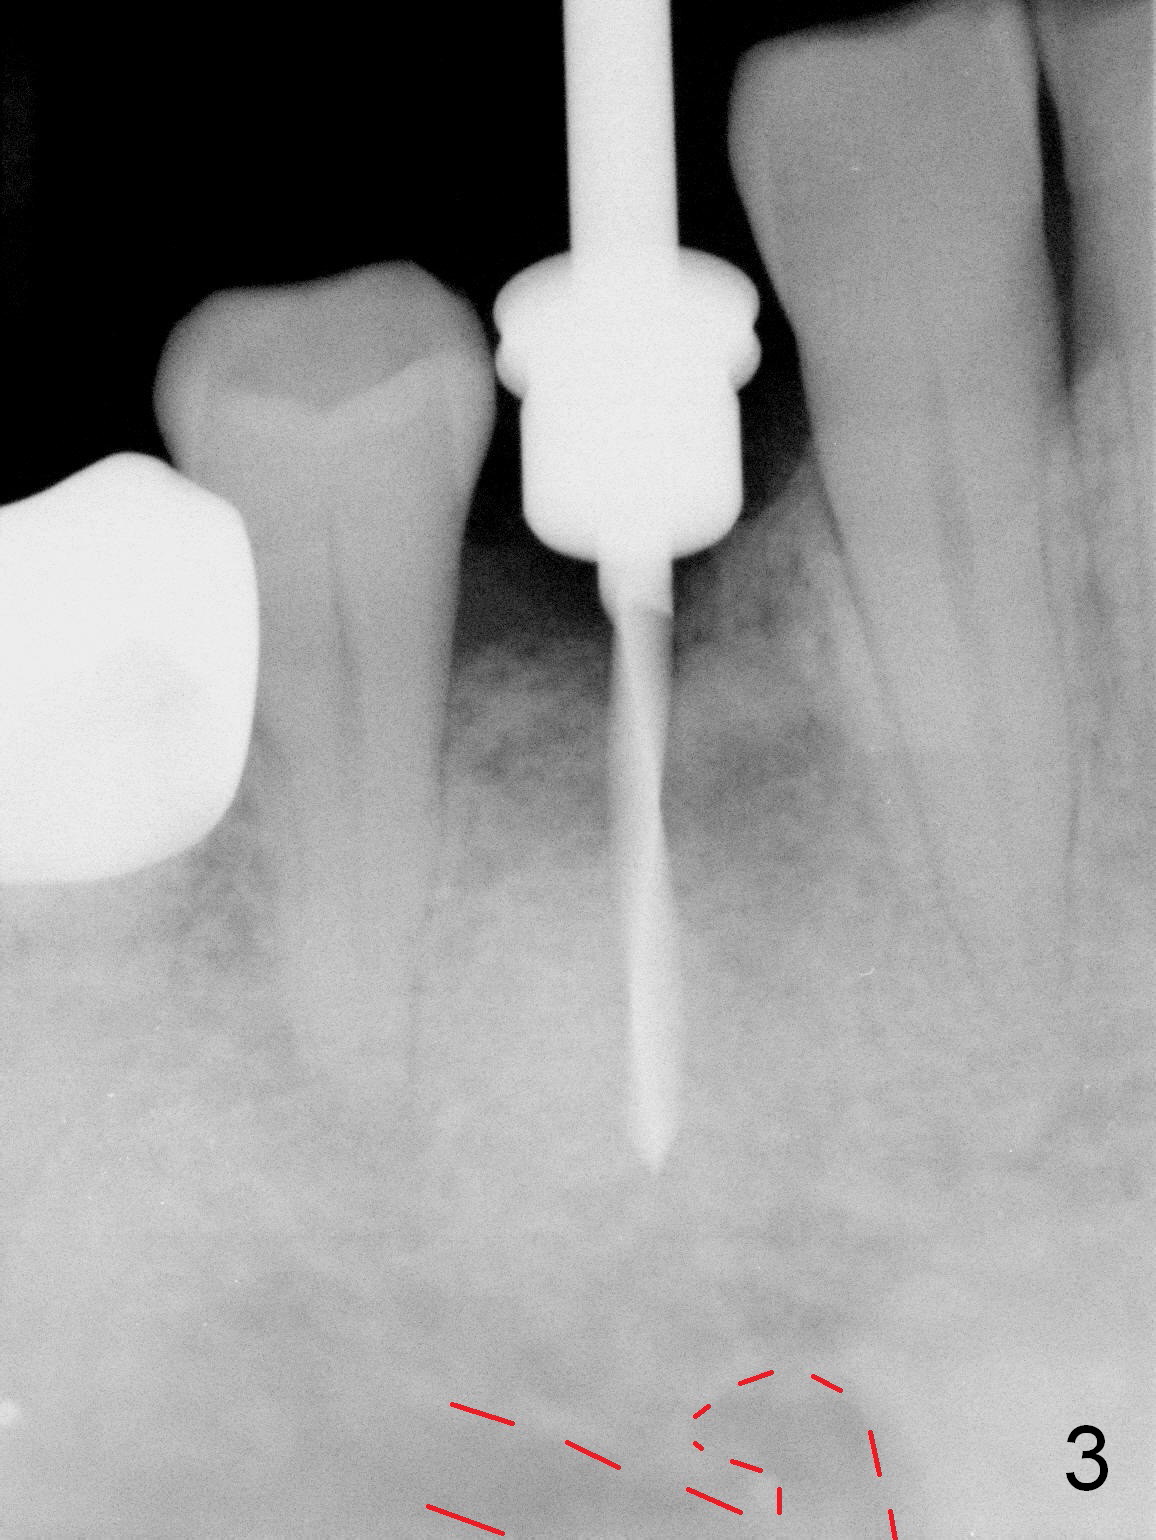

In fact the mesiodistal space of the site of #28 is within normal limit. The buccal plate atrophy is striking (Fig.1) with a fistula (^, associated with underlying residual root tip). When the flaps are raised, the ridge is triangular with the lingual plate (Fig.2 *) higher than the buccal one. Because of the slope, the multiple-drill approach is adopted in stead of single-drill one, because the marking bur is wobbling after 1.6 mm osteotomy at 13 mm (Fig.3). After placement of a 4x11 mm implant, a 4.5x4(2) mm abutment is inserted (Fig.4). The abutment and the implant act as a mesh (framework) so that bone graft and collagen membrane can be laid upon them buccolingually. When the flaps are sutured, there is less tension than that without the abutment. Furthermore, the buccal tissue volume seems to be increased (Fig.5 (<: fistula, which should heal soon), as compared to Fig.1). Tale photos to show effectiveness of the simultaneous GBR and disappearance of the fistula. Three months postop (Fig.6,7 (incomplete abutment seating)), the implant is loaded for intrusion of the opposing supraerupted tooth. The patient returns with chief complaint of food impaction between #27 and 28 three years 7 months post cementation; there is an open contact. Before pick up impression the distal convex surface of #27 is trimmed. The repaired crown has tight proximal contacts before (Fig.9,10) and after (Fig.11) retightening and cementation.